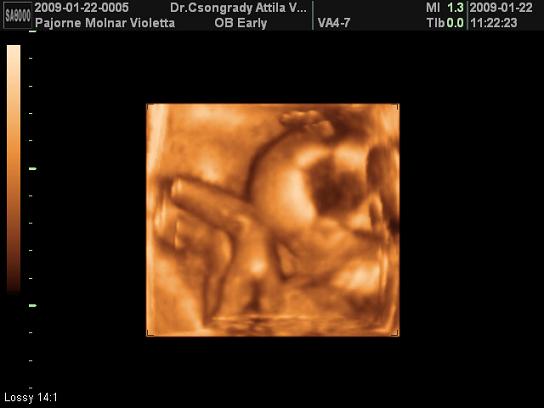

TEgnap voltam UH-n, mindjárt mutatok képet. Sajna Levente elég rossz néven vette, hogy zargatjuk, ahogy tudta takarta magát. Így nem sokat láttunk belőle, de azt megosztom Veletek.

Vivi, még csak most jelentetted be, hogy kisbabát vársz és már félidőnél tartasz. Nem semmi. Szépséges Levente, milyen szépen megmutatta magát! Nagyon klassz felvételek.